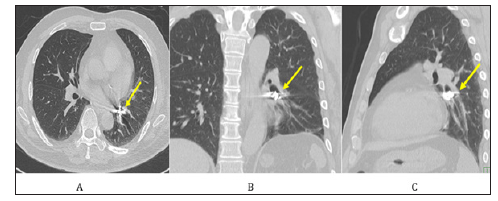

A 57-year-old male diagnosed with schizophrenia had been treated for tooth decay. During covering a dental crown, the palladium was dropped in the oral space. He had a continuous cough and was suspected of aspiration of the dental crown thus he was transferred to another hospital. Chest radiography showed a metallic foreign body in the left lower lung field (Figures 1A & 1B) and he visited the emergency department of our hospital. Chest computed-tomography showed an artifact, that is, a foreign metal body in the left basal segmental bronchus of B9 of the lung (Figures 2A-2C). An endobronchial foreign body was diagnosed, and endoscopic removal was scheduled as the first steps before surgical removal. Under airway anesthesia, a flexible bronchoscopy was guided to the stuck dental crown in the B9 endobronchus (Figure 3A), which was grasped (Figure 3B) and successfully removed by alligator forceps. As the dental crown is made of palladium with a smooth surface, and firmly fixed the peripheral bronchus, it should be difficult to remove, however, we could strongly grasp it using alligator forceps for a digestive endoscope.

Figure 2: Chest computed-tomographic scanning.

A. Metal artifact was shown in lesion of the left lower lobe (yellow arrow).

B. Metal artifact was located in the left lower and basal bronchus (yellow arrow).

C. Metal artifact was shown in the orifice of the left lower and basal bronchus (yellow arrow).

Regarding the diagnosis and treatment of foreign body aspiration is difficult to establish in adult subjects who present no a history of aspiration [8]. Most subjects with a history of foreign body aspiration present late to a medical facility (only 25% of subjects presented within 7 day of aspiration) [9]. Clinical suspicion of foreign body aspiration usually requires immediate admission to a hospital where the patient is initially studied by chest radiography to assess the presence of the foreign body or possible pleuroparenchymal and/or mediastinal changes [12]. Recent radiological literature has highlighted the diagnostic contribution of bronchoscopy [13], computed tomography (CT) [10], highresolution CT [14], spiral CT [15] and virtual bronchoscopy with multi-slice CT (MSCT) [16,17] in the evaluation of patients with suspected tracheobronchial aspiration of foreign bodies, leading to reconsideration of the role traditionally attributed to chest radiography [18]. Computed-tomographic scanning is a very useful method and there was no abnormal findings in 11% of the X-ray pictures [19]. CT is clearly more accurate than chest radiography in detecting radiolucent foreign bodies, and it should be performed in patients with a low level of clinical suspicion of foreign body aspiration in whom the chest radiography is negative [12]. In this case, computed-tomographic scanning could display the exact location of the foreign body (Figures 2A-2C).